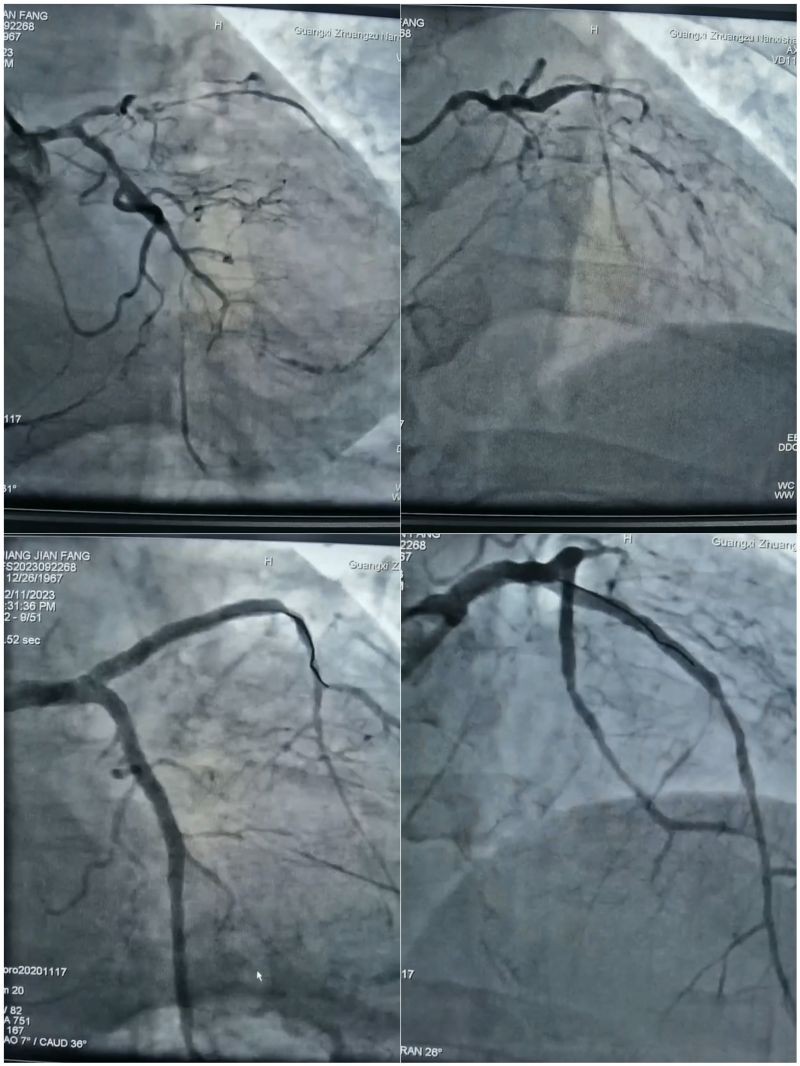

来自广西某县的蒋女士因心脏不适,在当地住院期间突发心衰,县医院紧急联系转院治疗。当救护车把蒋女士送到南溪山医院时,她的右冠状动脉急性闭塞,同时伴有急性左心衰发作,情况危急!心内科一病区的邓英松和张红雨两位副主任医师立刻进行急诊手术开通闭塞右冠,把她从鬼门关抢救回来。

检查发现,蒋女士出现急性心衰主要是因为冠脉病变。人的心脏有三大血管,分别是右冠状动脉、左冠状动脉(左主干)分流的左前降支和左回旋支,其中左冠状动脉供应着80%以上的心肌血量。蒋女士右冠状动脉急性闭塞的同时,前降支近段慢性闭塞,回旋支远段次全闭塞,严重影响供血,相当于一棵大树的主要枝干无法正常输送营养,树会枯萎。有数据显示,冠心病患者中超过70%的病例是由左主干狭窄造成的死亡。

目前治疗的主要手段有外科的动脉搭桥手术或微创介入的支架植入术,患者综合考虑选择了后者。作为蒋女士主诊医师的邓英松,已经有丰富的冠状动脉介入术(PCI)治疗经验,他知道蒋女士冠脉病变十分严重,手术难度系数和风险都极高。为确保治疗的安全性和精准行,邓英松采用先进的“血管内超声检查”技术,为患者精准定位支架位置,和介入团队详细制定了手术方案,经过多学科综合配合,一次性解决了左主干分叉病变+前降支慢性闭塞病变+回旋支次全闭塞病变,经造影检查右冠通畅,左冠形成良好循环供血,完全血运重建。目前患者恢复良好,准备出院。